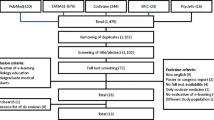

MR radiographers (n = 35) working in hospitals (n = 16) public and semi-public (military, academic) in Saudi Arabia participated (Table 2). The MR images (n = 25) reviewed by participants included images with several image quality errors as shown in Table 3.